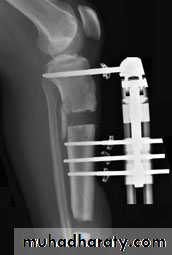

5. External fixation: its usually used in compound fr it means that we use a metal pins that pass through the skin from outside proximal and distal to the fr and after proper reduction the pins are joined together outside the skin by special long bars.The indications of external fixation:

Compound fractures.

Infected fractures as after internal fixation.

Multiple fractures, as an urgent way to stabilize a seriously ill patient.

Fr with nerve or vessel injury.

Fr with extensive soft tissue damage.

Fr of pelvis.

Seriously comminuted and unstable fr.

For bone lengthening.

For joint arthrodesis.

SKIN & SKELITAL TRACTIONSECROW FIXATION